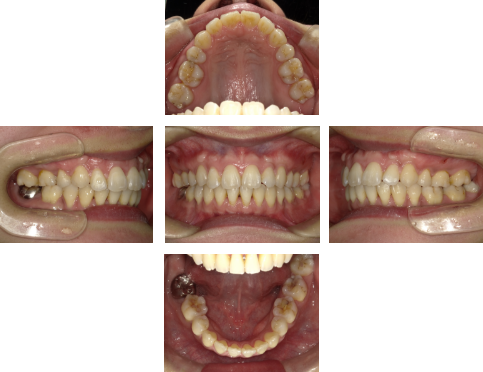

【初診時】

初診時の口腔内写真では、強い叢生(ガタつき)は目立ちません。しかし横から見た写真では、上下の前歯の前方突出が確認できます。

この症例では、歯を後方へ移動させるためのスペースが不足しているため、非抜歯では十分な改善が困難と判断しました。